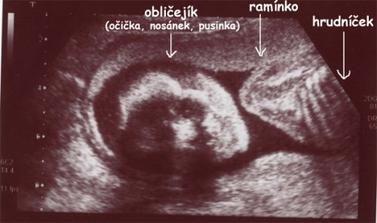

Čekání na Kateřinku... (UZ)

Čekáme holčičku - Kačenku. Dokud jsme jméno vybírali, říkali jsme jí Melounka. I.TP máme 29. 2., II.TP 2. 3. 2008. a III.TP je 13. 3. 2008.